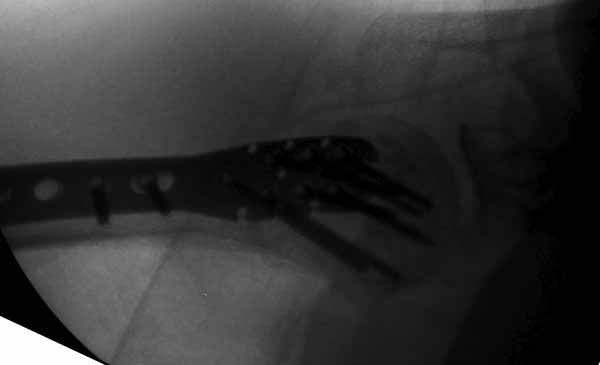

Набор мелких снимков не отражает истинную картину суставной поверхности лопатки, а также качество репозиции головки плеча. Необходимо доказать аксиальным снимком наличие покрытия головки. Правильная маркировка на рентген снимках и соответствие с выставленным диагнозом гарантирует от ошибок со стороной во время операции!

Здесь результат похожего случая, больная 87 лет, отягощенная сердечными делами и два года назад установка pacemaker и нескольких стентов. На третий день, сегодня утром сделали операцию. Послеоперационный псевдовывих связанный с релаксацией мышц и общим обезболиванием.